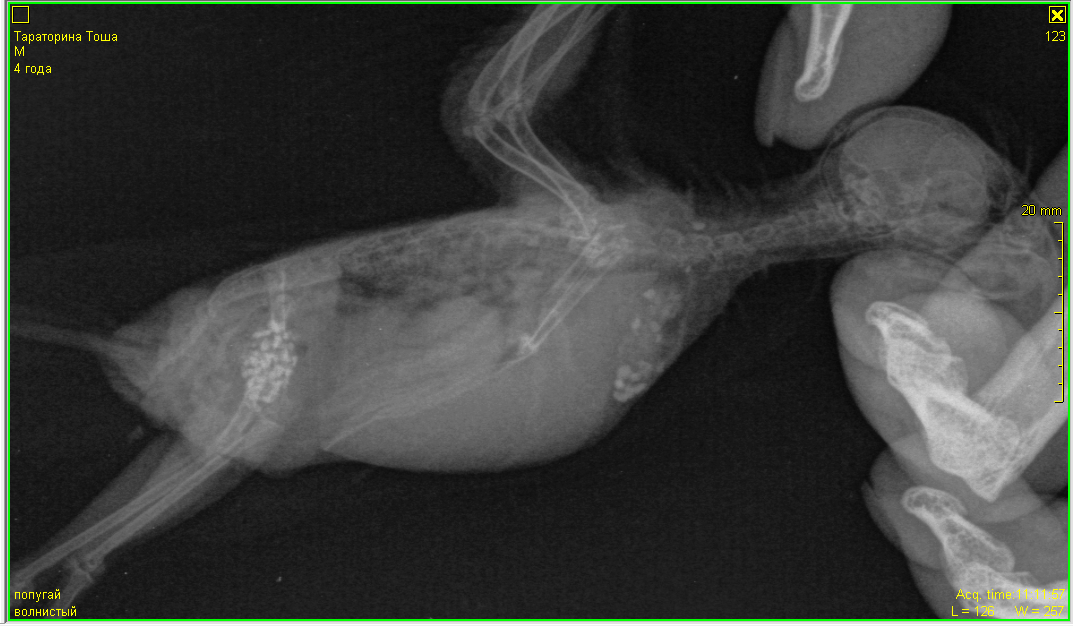

Вам встретился хороший доктор.

Диагноз (пневмония?+аэросаккулит) вполне возможен,судя по рентгену.

И травма левого крыла, в верхней трети плечевой кости- возможна. По лапе ничего не скажу- не видно.